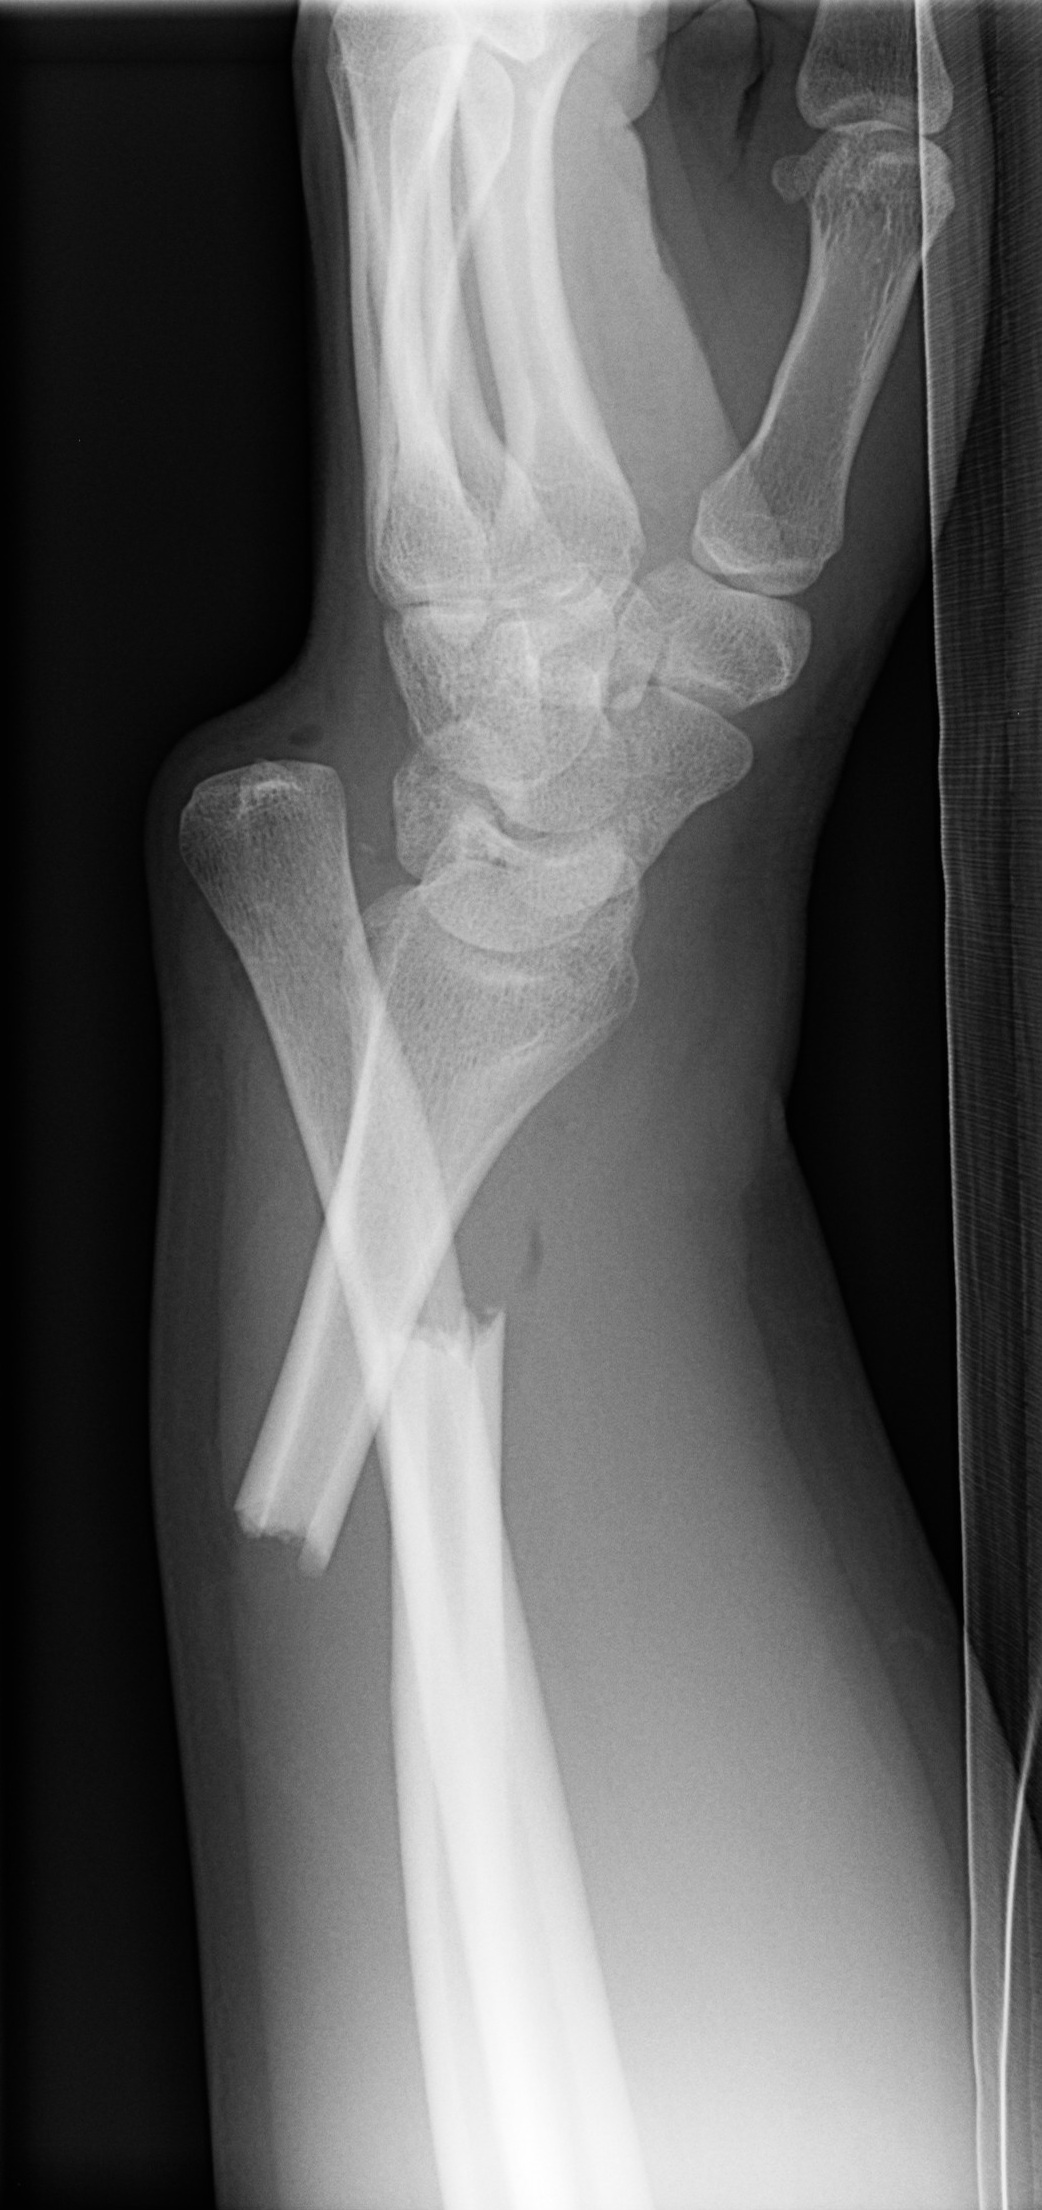

Colles Fracture

• Extra Articular fracture of distal radius with dorsal angulation (of the distal fracture fragment).

• Caused by FOOSH with extended wrist and pronated forearm.

Case courtesy of Frank Gaillard, Radiopaedia.org, rID: 12382 (Colles case)